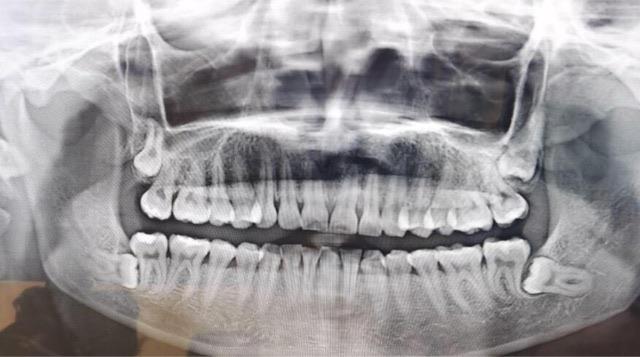

摘要:智齿,也称为第三磨牙,是人类的额外一对臼齿,通常在16岁至25岁之间开始出现。它们是人类进化的痕迹,起源于远古时期我们祖先的食物选择的变化。

智齿,也称为第三磨牙,是人类的额外一对臼齿,通常在16岁至25岁之间开始出现。它们是人类进化的痕迹,起源于远古时期我们祖先的食物选择的变化。然而,由于智齿的生长常伴随着问题和不适,许多人需要通过拔牙来解决这些问题。智齿的问题主要源于其冠部的生长问题。由于人类的口腔逐渐缩小,智齿往往没有足够的空间来正常生长和发育。

因此,智齿可能有以下几种情况:

1、闭合不全

智齿可能只部分穿透牙龈,这使得智齿难以清洁,易感染,导致疼痛和肿胀。

2、错位

智齿可能不在正确的位置上,可能向前倾斜、向后倾斜或垂直倒置。这些错位可能对邻近的牙齿造成压力和移位,导致不适和疼痛。

3、纵向堆积

智齿可能仅部分冒出牙龈表面,造成牙龈肿胀和不适。为了解决这些问题,许多人选择拔除智齿。根据情况的严重程度,医生会决定是否需要拔除智齿。完美的茶具礼仪语录拔除智齿通常是在局部麻醉下进行,医生会在口腔内提供适当的舒适度。